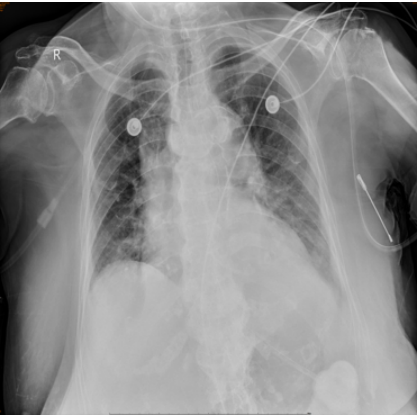

4月16日复查胸片可见两肺渗出逐渐吸收,左侧胸腔积液逐渐减少(图6)

图6  复查胸片较前好转(2024-04-16)